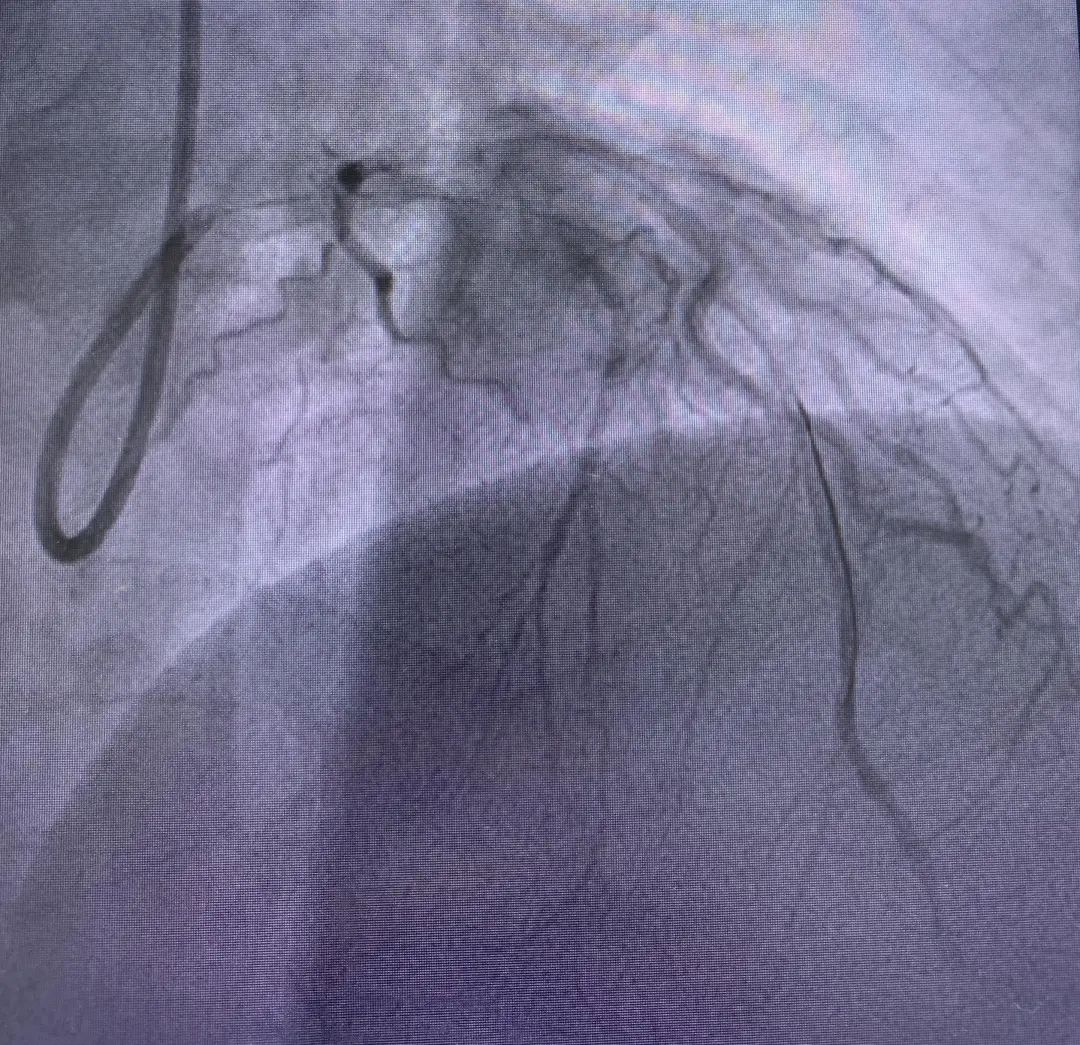

紧急行冠脉造影手术

术中进一步明确患者为

急性前间壁ST段抬高型心肌梗塞左主干+

双支病变累及前降支、回旋支

心血管内一科团队为患者实施了

前降支支架植入术及IABP(主动脉球囊反搏)术